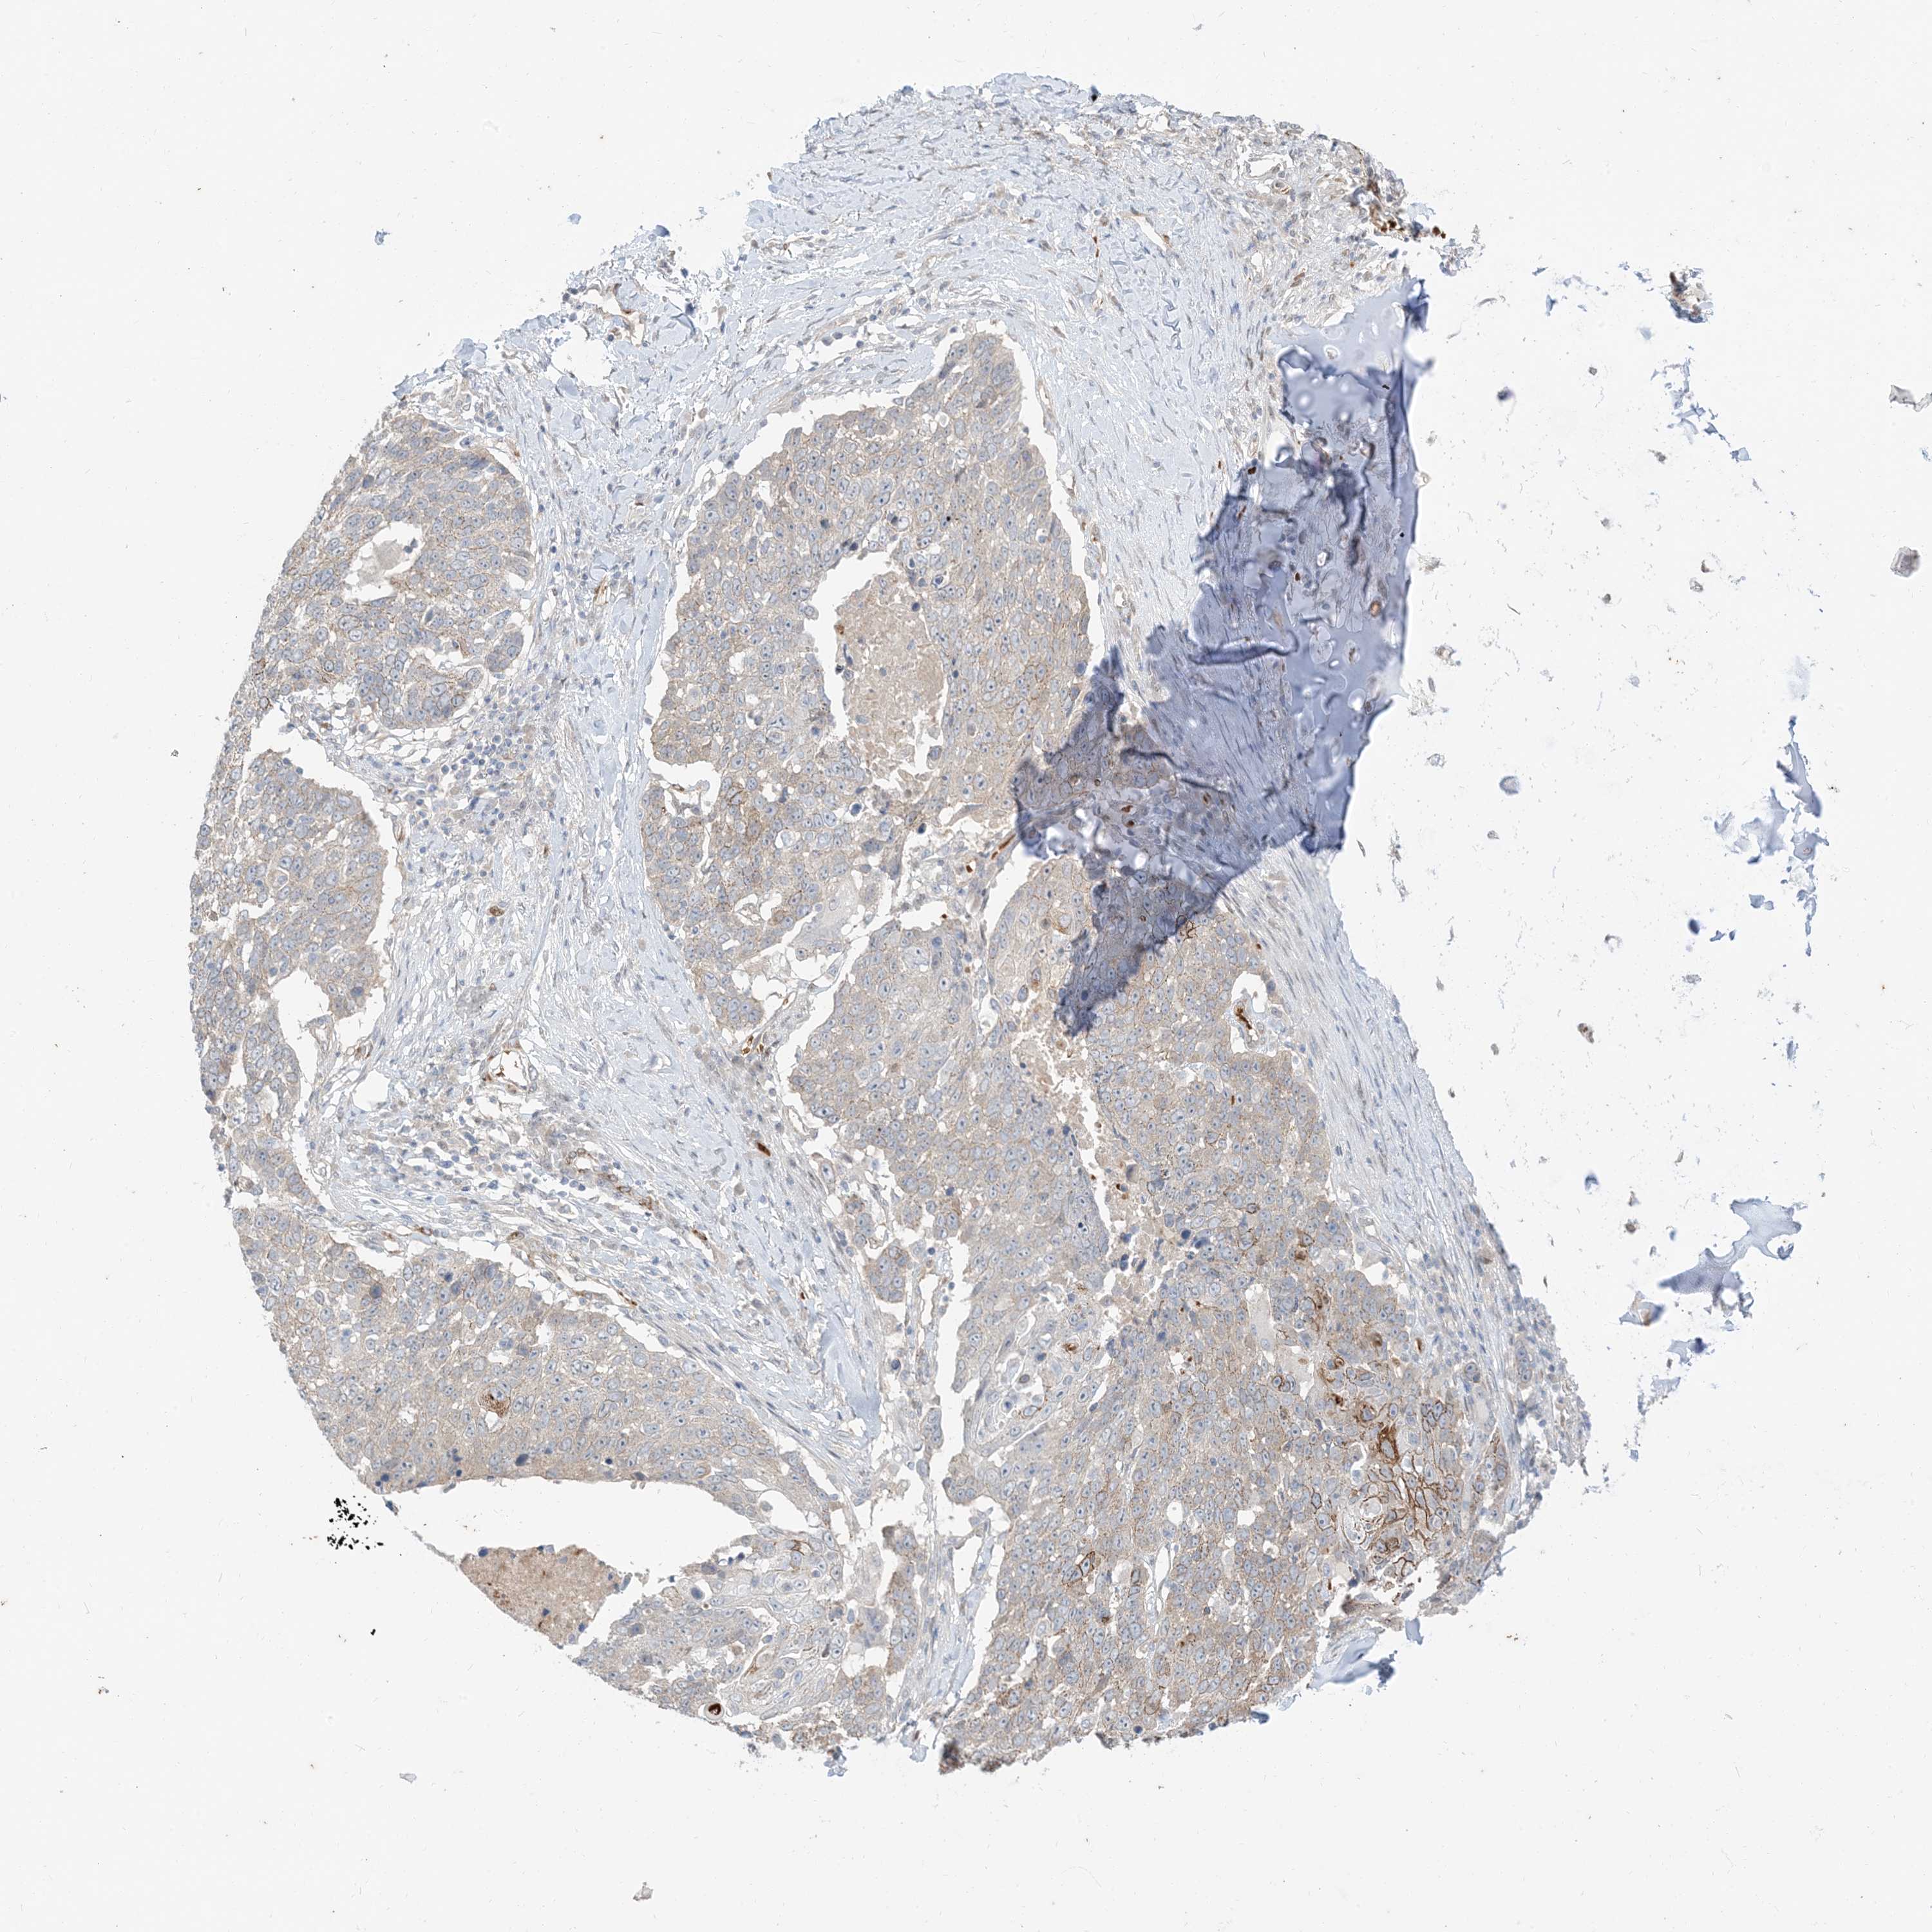

LUNG SQUAMOUS CELL CARCINOMA (TCGA) - Interactive survival scatter ploti

The Survival Scatter plot shows the clinical status (i.e. dead or alive) for all individuals in the patient cohort, based on the same data that underlies the corresponding Kaplan-Meier plots. Patients that are alive at last time for follow-up are shown in blue and patients who have died during the study are shown in red.

The x-axis shows the expression levels (FPKM) of the investigated gene in the tumor tissue at the time of diagnosis. The y-axis shows the follow-up time after diagnosis (years). Both axes are complimented with kernel density curves demonstrating the data density over the axes. The top density plot shows the expression levels (FPKM) distribution among dead (red) and alive patients (blue). The right density plot shows the data density of the survived years of dead patients with high and low expression levels respectively, stratified using the cutoff indicated by the vertical dashed line through the Survival Scatter plot. This cutoff is automatically defined based on the FPKM cutoff that minimizes the p-score. The cutoff can be changed by dragging the vertical line or by entering a cutoff value in the square labeled "Current cut-off".

Under the Survival Scatter plot the p-score landscape (black curve; left axis) is shown together with dead median separation (red curve; right axis). Dead median separation is the difference in median mRNA expression between patients who have died with high and low expression, respectively. It is calculated as follows: median FPKM expression of dead patients with high expression - median FPKM expression of dead patients with low expression. This is intended to aid the user in visually exploring custom cutoffs and the associated p-scores and dead median separation.

Individual patient data is displayed and can be filtered by clicking on one or more of the category buttons on the top of the page. Categories describing expression level and patient information include: high, low, alive, dead, female, male and tumor stages. The scale of the x-axis can be toggled between linear and log-scale by clicking on the "x log" button. Mouse-over function shows TCGA ID, patient information and mRNA expression (FPKM) for each patient.

& Survival analysisi

Kaplan-Meier plots summarize results from analysis of correlation between mRNA expression level and patient survival. Patients were divided based on level of expression into one of the two groups "low" (under cut off) or "high" (over cut off). X-axis shows time for survival (years) and y-axis shows the probability of survival, where 1.0 corresponds to 100 percent.

RIN1 is not prognostic in Lung Squamous Cell Carcinoma (TCGA)

Best expression cut offi

Based on the FPKM value of each gene, patients were classified into two groups and association between prognosis (survival) and gene expression (FPKM) was examined. The best expression cut-off refers the FPKM value that yields maximal difference with regard to survival between the two groups at the lowest log-rank P-value. Best expression cut-off was selected based on survival analysis .

When clicking on this number, the vertical dashed line indicating cut-off, the interactive survival plot, and the Kaplan-Meier curve will be adjusted to show results based on the best expression cut-off.

: 2.25

P scorei

Log-rank P value for Kaplan-Meier plot showing results from analysis of correlation between mRNA expression level and patient survival.

N/A

TCGA RNA samplesi

RNA-seq data is reported as average FPKM (number Fragments Per Kilobase of exon per Million reads), generated by the The Cancer Genome Atlas (TCGA) .

Normal distribution across the dataset is visualized with box plots, shown as median and 25th and 75th percentiles. Points are displayed as outliers if they are above or below 1.5 times the interquartile range. FPKM values of the individual samples are presented next to the box plot.

Average pTPM 5.4

Number of samples 489